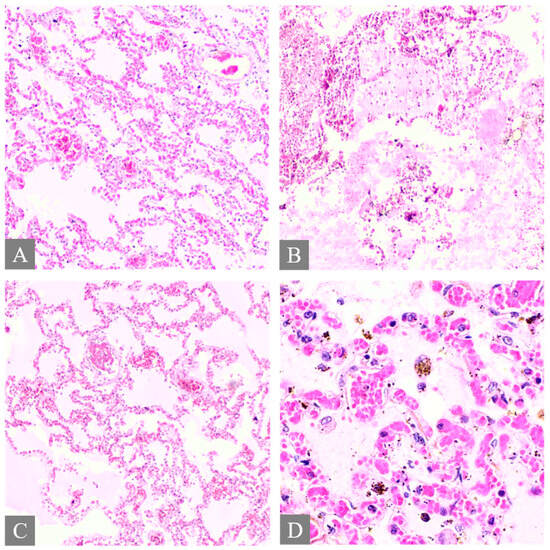

3.2. Microscopic Histopathological Findings

| 1 | N/A | Hemorrhage at subendocardial and myocardium | Edema | Steatosis | N/A | Partial autolysis | Partial autolysis | N/A |

| 2 | N/A | N/A | N/A | Steatosis | N/A | N/A | N/A | N/A |

| 3 | Subarachnoid congestion, hemorrhage, eosinophilic neurons | Thrombosis, myocardial necrosis, focal subendocardial hemorrhage, atherosclerosis | Diffuse alveolar damage, fibrin platelet thrombi | Multifocal ballooning degeneration (hepatocyte), steatosis | Congestion | Acute tubular necrosis, fibrin platelet thrombi in glomeruli | Focal cortical necrosis | Mucosal infarct, hemorrhage |

| 4 | N/A | N/A | Edema, congestion, petechial hemorrhage | Steatosis | Congestion | N/A | N/A | Mucosal hemorrhage, esophagitis |

| 5 | N/A | Atherosclerosis | Diffuse alveolar damage, hemorrhage, fibrosis | Cholestasis | N/A | Acute kidney injury | N/A | N/A |

| 6 | N/A | Myocardial infarction, coronary occlusion | Edema, congestion, petechial hemorrhage | N/A | N/A | N/A | Lipid depletion | Mucosal infarct, hemorrhage |

| 7 | Red blood cells within the subarachnoid space | Cardiomegaly, hemorrhage at myocardium | Edema, congestion, | Steatosis | Congestion | N/A | Lipid depletion of cortical cells | Superficial mucosal hemorrhage |